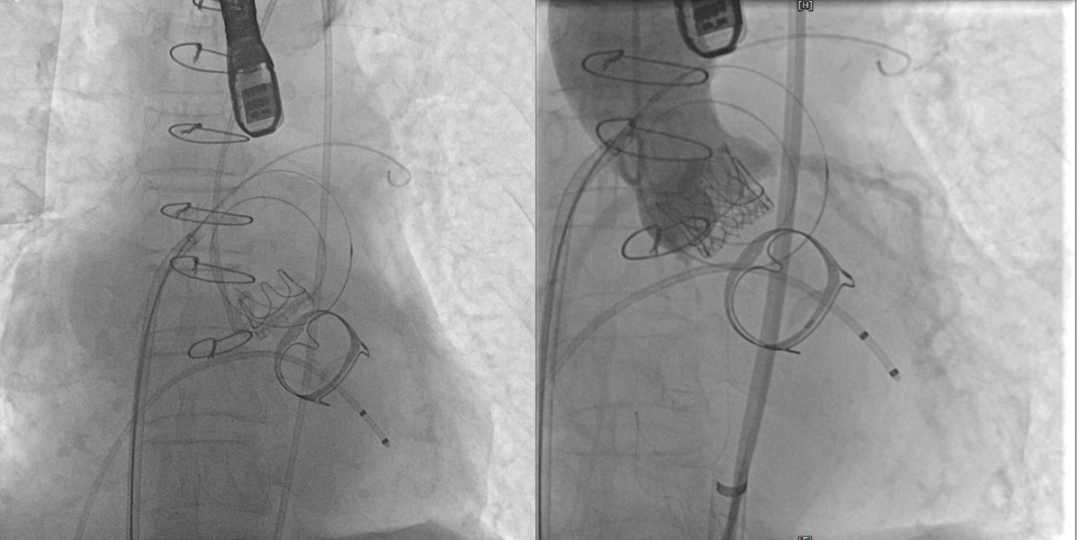

术前(图1)和TAVR 植入(图2)